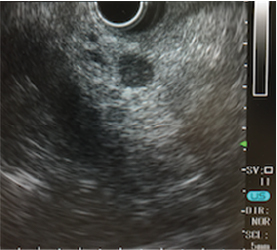

EUSは、内視鏡(胃カメラ)の先端に超⾳波観測装置(エコー)を装着しており、膵臓を最も詳しく観察できる検査機器です。5年⽣存率8%とされ、最も⼿ごわいと⾔われる膵がんも1cm以下で発⾒されれば、5年⽣存率は80%です。こうした早期の膵がんを⾒つけるのに不可⽋な最新鋭の検査がEUSです。その他にも、胆嚢がんと胆管がんの治療⽅針を決める上でも重要な情報を得ることができます。

超⾳波内視鏡で対象病変を観察しながら針⽣検を⾏うのがEUS-FNAです。これまで病理診断のための検体採取が難しいとされてきた腫瘤‧膵臓のリンパ節の検体採取が安全かつ簡便に⾏えます。サテライトでは世界トップクラスの実績を有する医師とそのチームが検査を担当します。

超⾳波内視鏡下針⽣検(EUS-FNA)による診断

9.6mmの膵臓腫瘍

胃の中から直接、細い針で腫瘍の組織を安全に採取しています